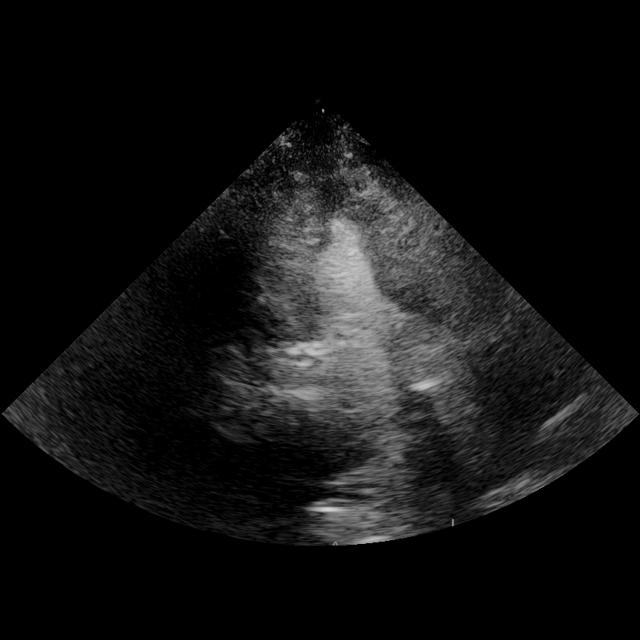

View and measurement extraction

We structure each study to mirror clinical reading: a pretrained classifier assigns standardized views, followed by quantitative measurement extraction. Views are categorized using the American Society of Echocardiography (ASE)–defined classes (mitchell2019guidelines). To extract quantitative parameters, we crop the clinically annotated measurement overlays from the image and transcribe them into structured JSON using Qwen2.5-VL-72B (qwen2.5-VL; Qwen2VL). The resulting fields include chamber dimensions, transvalvular gradients, and Doppler ratios.(Fig. 2a). Extraction fidelity was verified by manual review.